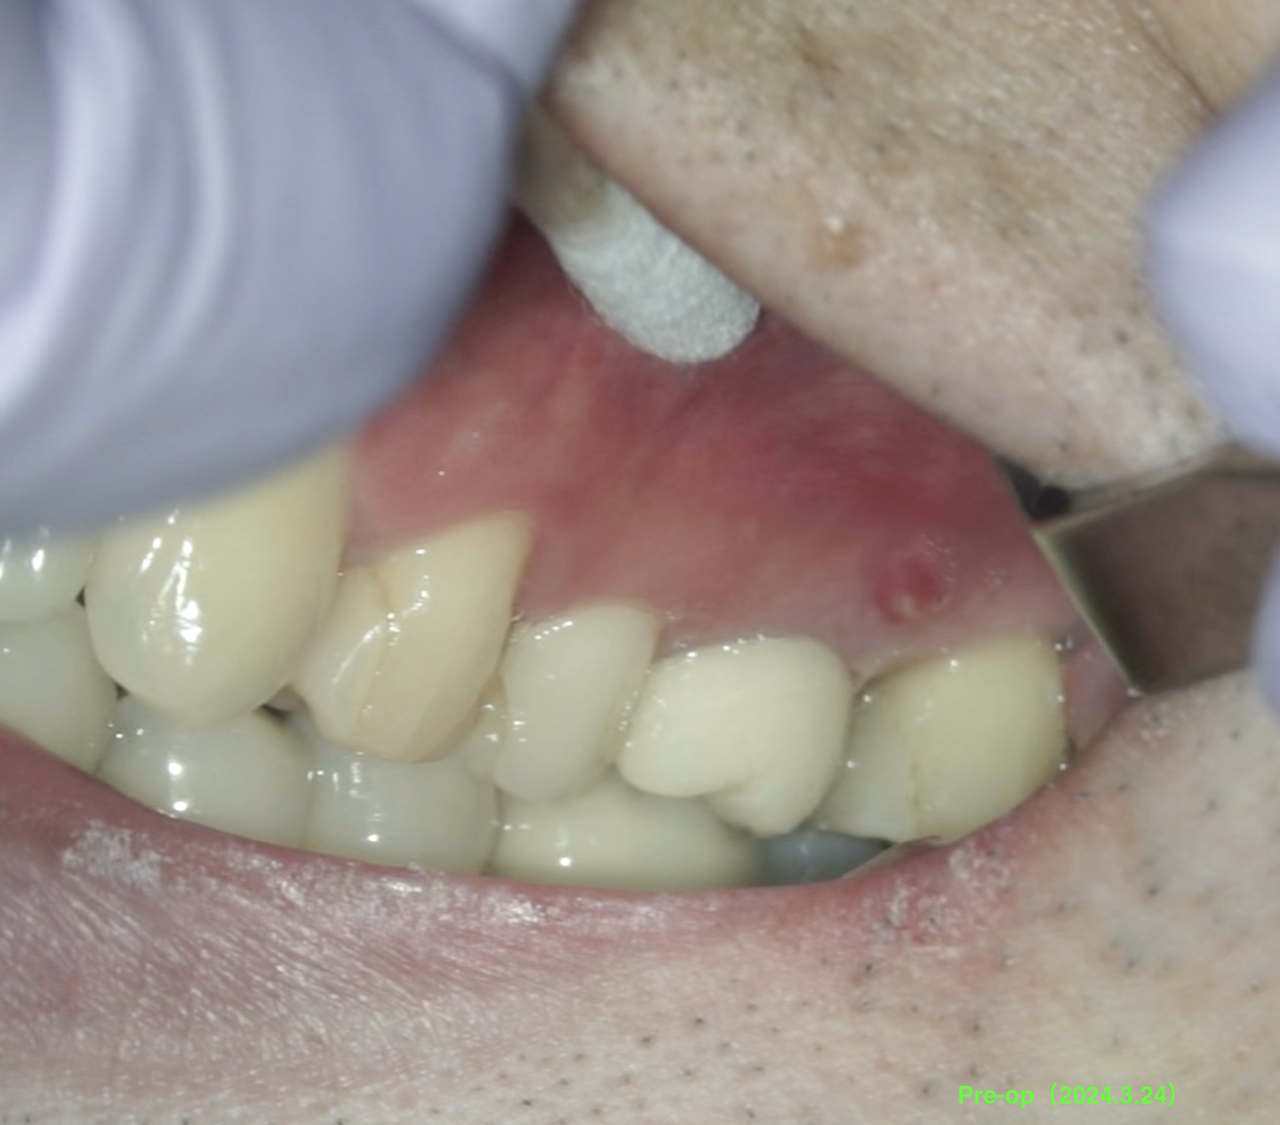

術前にSinus tractがあり、

そして、頬側の歯槽骨がほとんどない。

術前のSinus tractは消失した。